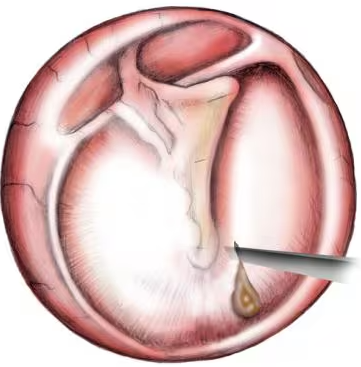

- Myringotomy for chronic middle ear fluid

- Removal of growths or polyps if present